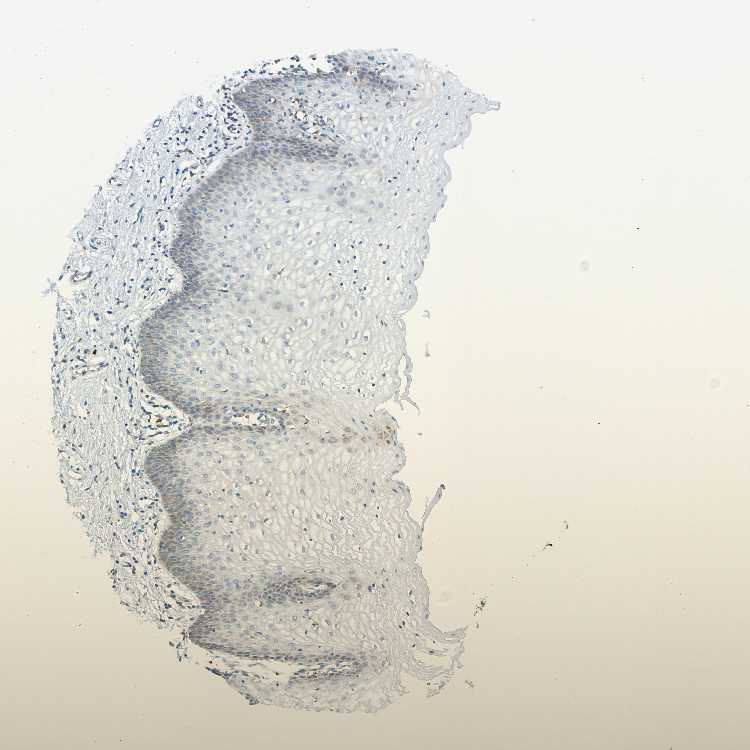

TISSUE PRIMARY DATA VAGINA Show tissue menu

VAGINA - Antibody stainingi

Antibody staining in the annotated cell types in the current human tissue is reported as not detected, low, medium, or high, based on conventional immunohistochemistry profiling in selected tissues. This score is based on the combination of the staining intensity and fraction of stained cells.

Each image is clickable and will lead to virtual microscopy that enables deeper exploration of all samples and also displays staining intensity scores, fraction scores and subcellular localization as well as patient and tissue information for each sample.

Antibody HPA011276Antibody HPA017062

Squamous epithelial cells LowNot detected